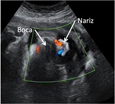

Mueve la boca y la mandíbula

Con 29 semanas de gestación el feto mueve su boca y barbilla en esta ecografía en 4D. Son movimientos que podrían interpretarse como si tragase líquido amniótico. Y es probable que lo haga, ya que su sistema digestivo está preparado para digerirlo desde finales del primer trimestre.